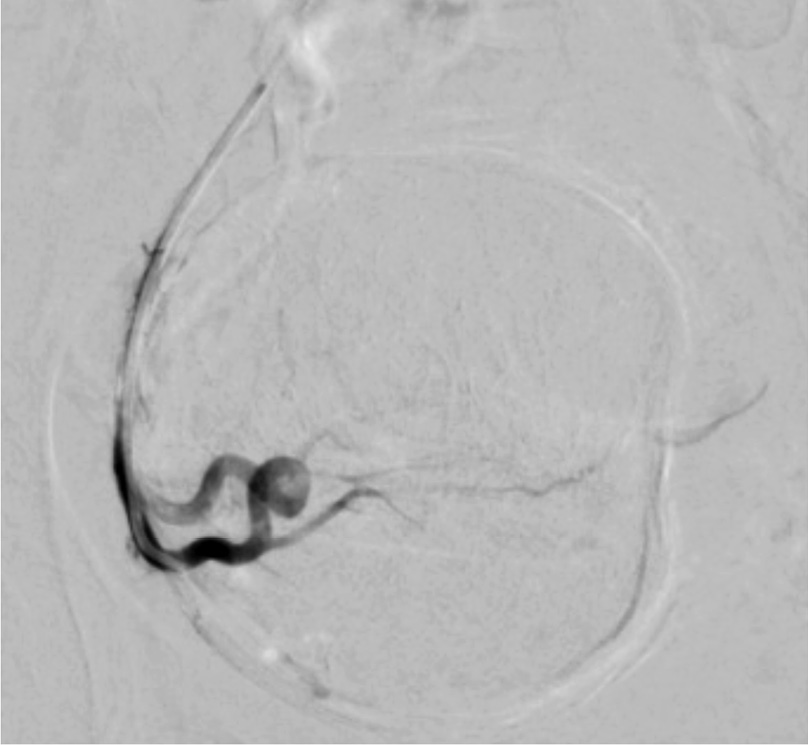

Выполнены пункция и катетеризация правой лучевой артерии в ретроградном направлении. Далее катетером выполнена селективная катетеризация правой и левой маточных артерий. Выявлена миома матки больших размеров с выраженным перифиброидным сплетением. При проведении ангиографии брюшной аорты и таза дополнительных источников кровоснабжения не выявлено. Катетер по проводнику проведен последовательно в горизонтальные сегменты левой и правой маточных артерий, питающих узлы (рис. 2, 3). Проведена эмболизация насыщенными гадотеридолом микросферами до стаза контраста в дистальных сегментах маточных артерий. Рентгеновский контроль эффективности эмболизации – на рис. 4, 5. Катетер и интродьюсер удалены. Наложена давящая асептическая повязка.

Рис. 2. Клинический пример №1. Ангиограмма правой маточной артерии до ЭМА. / Fig. 2. Clinical case 1. Angiogram of the right uterine artery before UAE.

Рис. 3. Клинический пример №1. Ангиограмма левой маточной артерии до ЭМА. / Fig. 3. Clinical case 1. Angiogram of the left uterine artery before UAE.